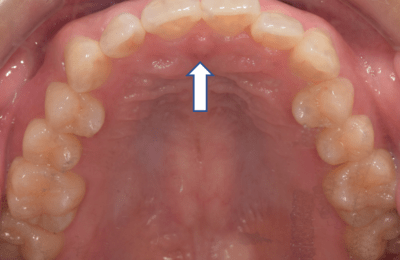

✓舌が上顎に挙がっている

舌が下に落ちている場合

(お口ポカン、歯ぎしり食いしばりが多い、舌で歯を押してしまう方)

→舌の正しい位置を把握するトレーニング

安静時、舌の先は正しい位置にありますか?

舌をいつもつけておく位置を覚えましょう

- 上の前歯の1cm内側の歯ぐきのくぼみに舌の尖端をおく。

- 舌全体を上あごにつける

→舌全体を口蓋に挙げるトレーニング

①舌全体を口蓋に吸いつけ、ゆっくりと開ける

②ポンと舌打ちをする

③30回繰り返す

※舌の先はスポットにつけ、丸めないように注意しましょう!